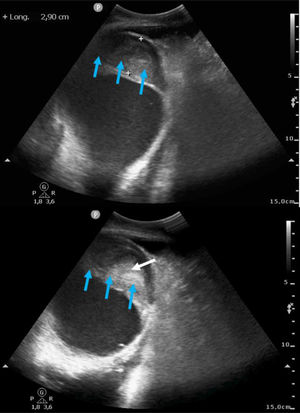

This is the case of a 61-year-old woman who had a myocardial infarction one month prior and subsequently developed post-infarction mechanical complications. The echocardiogram revealed the presence of a large apical pseudoaneurysm (Figs. 1 and 3: blue arrow) (Appendix A Video), with a 2.93cm neck (Figs. 1 and 2: yellow arrow) and free flow of echocontrast through it (Fig. 2: red arrow). The lumen was partially thrombosed (Figs. 1 and 3: white arrow). She also exhibited severe left ventricular dilatation and very severe global systolic dysfunction (Fig. 1) (LVEF 11%; LVOT VTI 7cm). Forty-eight hours after admission, the patient developed SCAI C-D cardiogenic shock, requiring mechanical support with V-A ECMO and an intra-aortic balloon pump, which led to a significant improvement in organ perfusion. After coordination with the referral hospital, she underwent a code 0 heart transplant, with a favorable recovery. This case highlights the importance of echocardiographic diagnosis and mechanical support management in critical situations of cardiogenic shock.